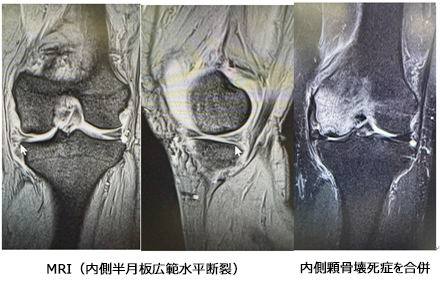

■ 半月板修復術(Meniscus Repair)/ 切除術

- 適応疾患: 半月板損傷(膝の曲げ伸ばし時の痛み、引っかかり感、ロック現象など)。

- 手術概要: 半月板は膝のクッションやスタビライザーとして重要な役割を果たします。損傷部位や形態に応じて、可能な限り修復術(縫い合わせる手術)を選択し、半月板の温存に努めます。血流が悪く修復が難しい場合や、損傷が広範囲に及ぶ場合は、痛みの原因となっている部分を最小限切除する切除術を行います。いずれも関節鏡視下手術で行われます。